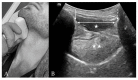

Airway management is a common and critical procedure in acute settings, such as the Emergency Department (ED) or Intensive Care Unit (ICU) of hospitals. Many of the traditional physical examination methods have limitations in airway assessment. Point-of-care ultrasound (POCUS) has emerged as a promising tool for airway management due to its familiarity, accessibility, safety, and non-invasive nature. It can assist physicians in identifying relevant anatomy of the upper airway with objective measurements of airway parameters, and it can guide airway interventions with dynamic real-time images. To date, ultrasound has been considered highly accurate for assessment of the difficult airway, confirmation of proper endotracheal intubation, prediction of post-extubation laryngeal edema, and preparation for cricothyrotomy by identifying the cricothyroid membrane. This review aims to provide a comprehensive overview of the key evidence on the use of ultrasound in airway management. Databases including PubMed and Embase were systematically searched. A search strategy using a combination of the term "ultrasound" combined with several search terms, i.e., "probe", "anatomy", "difficult airway", "endotracheal intubation", "laryngeal edema", and "cricothyrotomy" was performed. In conclusion, POCUS is a valuable tool with multiple applications ranging from pre- and post-intubation management. Clinicians should consider using POCUS in conjunction with traditional exam techniques to manage the airway more efficiently in the acute setting.